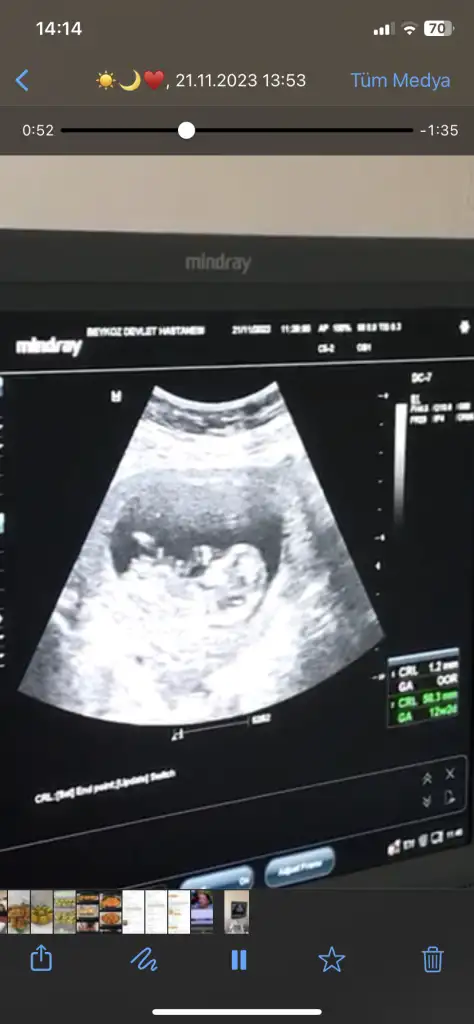

Benimkine de bakabilir misiniz doktorum 11+5te kız dedi 13+6da erkek dedi

İlk 3 fotoğraf 13+6

Son 2 fotoğraf 11+5

• Screenshot_2023-11-22-12-45-30-753_com.miui.gallery.webp

Screenshot_2023-11-22-12-45-30-753_com.miui.gallery.webp

15,1 KB · Görüntüleme: 207